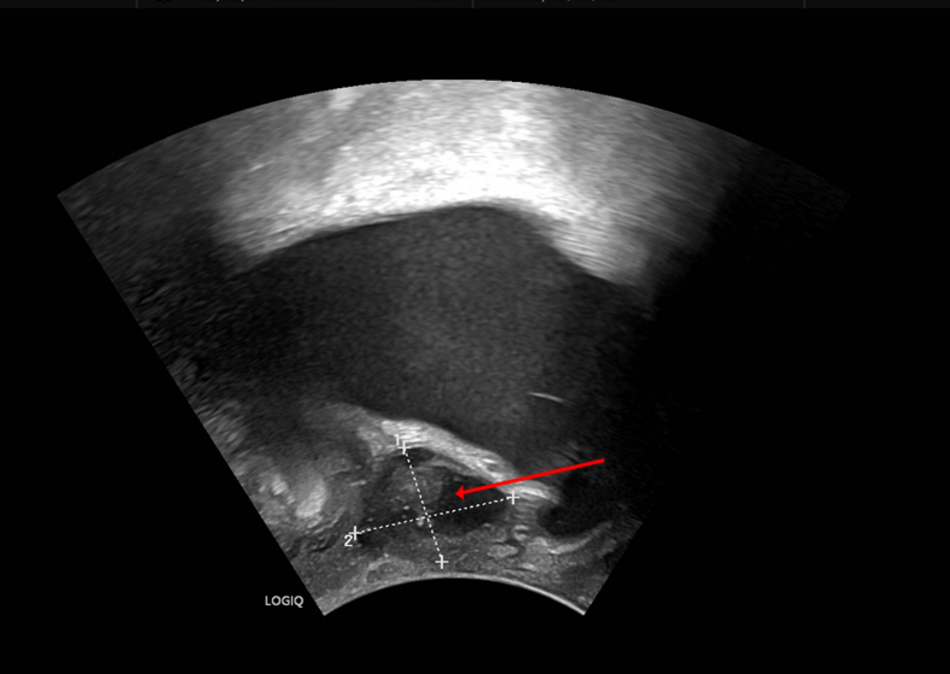

Bis einschließlich Donnerstag, 26. Februar 2026 bietet die Ärztekammer Nordrhein allen Ärztinnen und Ärzten im deutschsprachigen Raum eine kostenlose Online-Fortbildung an. Das aktuelle Thema lautet "Unklare Raumforderung zwischen Vagina und Urethra bei einer 62-jährigen…